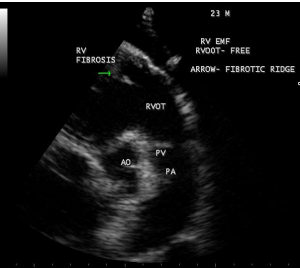

Figure 15: RV outflow tract is free of fibrosis and fibrous strands stand as ridge in Endomyocardial fibrosis with tuberculosis.

Case 2 (Right ventricular endomyocardial fibrosis in Tuberculosis) A 23-year old male was admitted with sudden onset of ascites for one-month duration. He was treated for pulmonary tuberculosis 3 years back with a positive sputum AFB (acid fast bacilli). Blood chemistry revealed as ( Total count-7400 cells/cu.mm of blood ( normal-4000 to 11000 cells/cu.mm of blood), polymorphs -70% (normal- 40 to 75 %), lymphocytes-22%(normal-20 to 40%), eosinophils-8% (normal- 1 to 4%), ESR (erythrocyte sedimentation rate)-10 to 22 mm/hour ( normal- 0 to 15mm/hour), platelets-2.5 lakhs/cu.mm of blood and a mild elevation of serum bilirubin-total-2mg/dl(normal---up to 1.2 mg/dl) direct-1.2mg%(normal—upto—0.3 mg/dl), indirect-0.8mg%(normal – upto 0.9 mg/dl). Total serum proteins 5.2gm% (normal -6.6 to 8.3 gm/dl), albumin-3.2gm% (normal- 3.5 to 5.0 gm/dl), globulin -2.0gm%(normal 2.5 to 3.5 gm/dl ), urea-39 mg%(normal 15-50 mg/dl), creatinine-0.1mg%(normal- 0.7 to 1.4mg/dl), sugar-112 mg/dl random (normal – 80 to120 mg/dl- random sample). Ascites fluid tapping revealed an exudate (protein-3 gm%) and cytology revealed no malignant cells. Ascites fluid adenosine deaminase (ADA)activity revealed 10.4 U/L (normal < 40>Figure 8. His pulse rate was 108 bpm and blood pressure 100/70 mmHg. Auscultation revealed clear lung fields and no cardiac abnormalities. ECG revealed no arrhythmias and X-ray chest showed right- sided pleural effusion and extensive calcification over the cardiac shadow as shown in Figure 9. Transthoracic echocardiography revealed apical fibrosis of right ventricle, moderate pericardial effusion, right atrial dilatation as shown in Figures 10 and 11, suggesting right ventricular endomyocardial fibrosis and severe tricuspid regurgitation as in Figure 12 indicates coexisting pulmonary hypertension due to pulmonary damage caused by tuberculosis as shown in Figure 13 and free RV outflow tract as in Figure 15. Patient was treated with antituberculous drugs, antifailure measures such as digoxin and diuretics, ascites fluid tapping and antibiotics. He showed mild improvement in his symptoms.